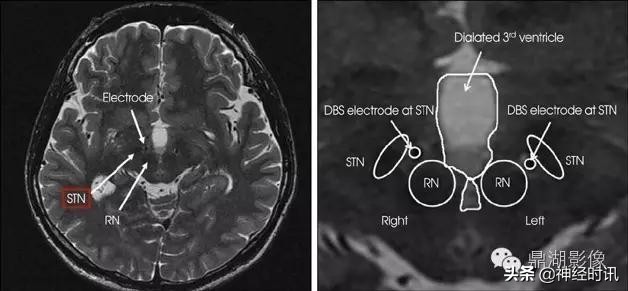

丘脑底核

即Luys核,为一梭状结构,位于间脑的基部和中脑脚的移行处,中脑大脑脚的背面,正好是内囊转入大脑脚的转折处。目前认为它可能为黑质的延续。在人类中此核较大。

红核

左右各一,位于中脑中线的两侧,黑质之背内侧。横断面呈微红色的圆形核团,接受小脑的神经纤维,并发出红核脊髓束。红核及其联系神经受损时,可引起小脑性动作性震颤或小脑性共济失调。